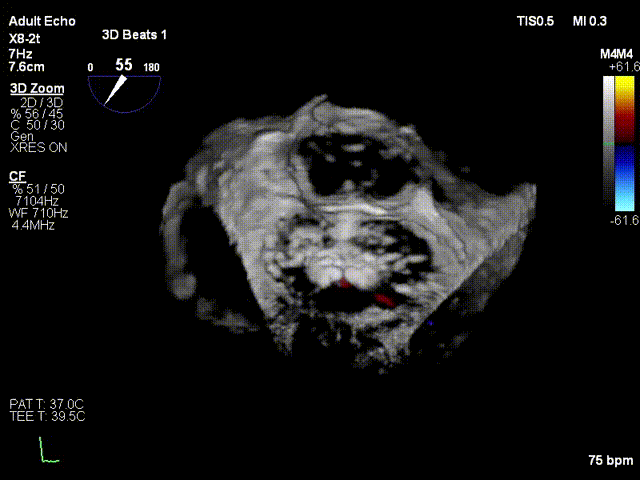

术前3D彩色

二尖瓣交界联合彩色

反流主要来源于2区累及1、3区